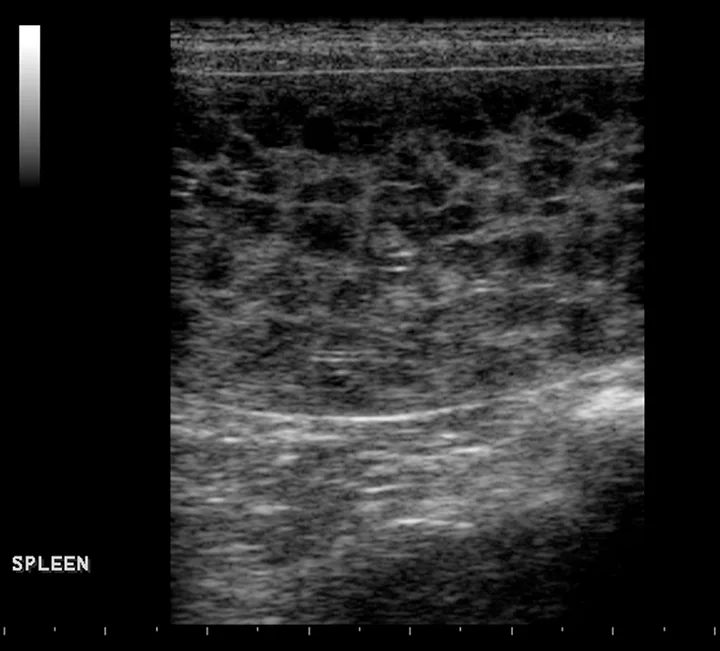

FIGURE 6

The spleen is markedly enlarged, hypoechoic, and lacy, with hyperechoic patches surrounding the hilus. A perivenous hyperechoic triangle at the splenic hilus is continuous with the mesentery, and no flow is present on Doppler. These findings are often associated with splenic torsion.20